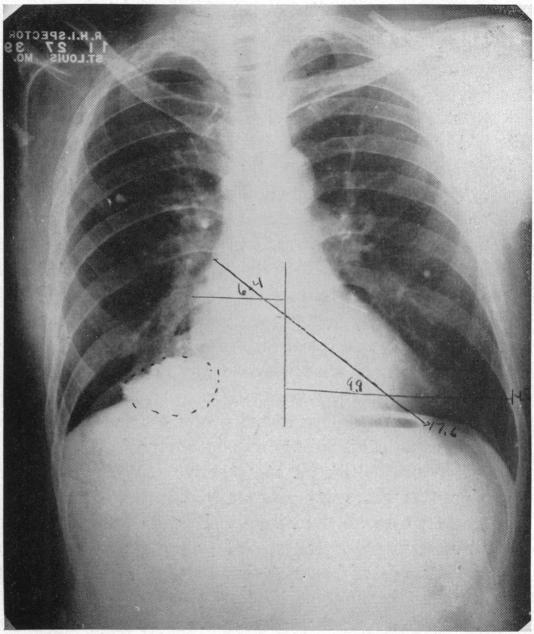

CONGENITAL ARTERIOVENOUS ANGIOMA OF THE ARM: METASTASES ELEVEN YEARS AFTER AMPUTATION.

Ann Surg. 1940 Jun;111(6):1021-45. doi: 10.1097/00000658-194006000-00009.